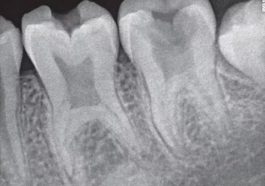

Lee Gay Lord – Taurodontia adalah kelainan bentuk gigi geraham yang ditandai ruang pulpa membesar dan akar gigi lebih pendek …